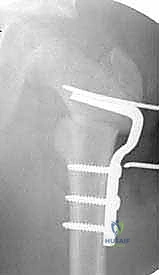

6. إدخال الشريحة والتثبيت (Plate Insertion & Fixation)

يتم إدخال نصل الشريحة ذات الزاوية 90 درجة في المسار الذي تم تحضيره في عنق الفخذ. ثم يتم ضم جزئي العظم المقطوعين معاً (إغلاق الفجوة)، مما يؤدي فوراً إلى تغيير زاوية عنق الفخذ إلى الوضع الطبيعي الجديد. يتم تثبيت الجزء الطويل من الشريحة على جسم عظم الفخذ باستخدام براغي قوية من التيتانيوم أو الفولاذ الطبي المقاوم للصدأ.

بعد التأكد من صلابة التثبيت ووضعية المفصل المثالية عبر الأشعة، يتم غسل الجرح وإغلاقه بطبقات متعددة باستخدام خيوط تجميلية لتقليل الندبات.

لماذا الشريحة ذات الزاوية 90 درجة (90-Degree Blade Plate) تحديداً؟

قد يتساءل البعض: لماذا يصر الأستاذ الدكتور محمد هطيف على استخدام هذا النوع المحدد من الشرائح في عمليات قطع عظم الفخذ الداني التقويمي؟ الإجابة تكمن في الميكانيكا الهندسية:

- التثبيت فائق الصلابة (Rigid Fixation): النصل العريض للشريحة الذي يدخل في عنق الفخذ يوفر ثباتاً دورانياً وزاوياً لا مثيل له، مما يمنع العظمة من التحرك أثناء فترة الالتئام.

- التحكم الدقيق في الزوايا ثلاثية الأبعاد: تسمح هذه الشريحة بتصحيح زاوية الميل (Varus)، وكذلك تصحيح الدوران الخاطئ للعظمة (Derotation) في نفس الوقت.